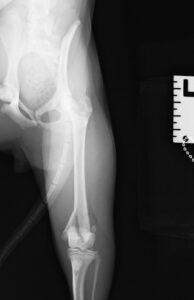

9ヶ月の柴犬の女の子が、高所から落下してしまい左後肢を痛めたとのことで来院されました。左後肢は足を着くことができず、レントゲン検査の結果、大腿骨(太ももの骨)の複雑骨折を認めました。

大腿骨の膝に近い部分が骨折してしまっており、さらに単純な骨折ではなかったため、内側と外側にそれぞれプレートを設置し固定しました。

大腿骨遠位の骨折は特に若齢の犬猫においてしばしば発生します。若齢時には多くの骨の両端に成長板という骨を作る場所があり、その場所は強い力がかかった際に骨折しやすいためです。単純な骨折の場合にはピンだけで整復が可能なことも多くありますが、今回のような状況ではプレート固定も適応になります。どちらにしても手術後に関節の拘縮が起きやすく、術後のリハビリも重要になってきます。当院ではリハビリに特化したスタッフも在籍し、術後のケアもご家族と共に実施していきますので安心して手術を受けて頂くことができます。